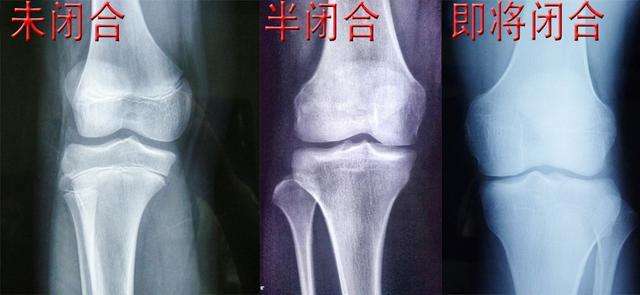

17~20岁的青少年,骺板的软骨细胞停止分裂,骺软骨逐渐完全被骨组织取代,在长骨的骨干和骨骺之间留下线性痕迹,称作骺线。

在骨骺闭合后,长骨不会继续纵向生长。全身长骨的骨骺闭合时间不一致,比如腕骨骨骺闭合时间因年龄而有差异,这是评估骨龄的重要依据。在重大刑事案件中,通过骨龄鉴定对于判断年龄有很大帮助。但是,骨干仍然可以继续增粗,骨干外表面的新骨形成速度快于骨干内部吸收速度,这样骨干的密致骨逐渐增厚。人到30岁左右,长骨不再增粗。随着年龄增长,骺骨逐渐闭合,但是骨干可以继续增粗。

如果一个人的骨头发育没有那么好,或者中途出了什么差错,这个人并不会长得太高,身材也会小个一些。在人体的所有骨头中,腿部尤其是膝盖部分的骨头和人体的长高关系最大。这个部分的骨头中间有一层很软的骨头叫做软骨。随着年龄的增长和人体的发育,软骨也会逐渐变硬或者骨化,一旦软骨完全成骨化的状态人就不太可能还可以增高了。可不可以控制软骨不要让它骨化呢?这是不可能的,随着年龄的增长长高,人体也会慢慢被骨化,一旦骨头闭合了,人的骨头生长发育也就停止了,人也就无法再长高。这是不可改变的事实,每个人都会经历相同的阶段,所以我们应该面对现实。